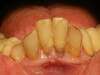

cas n°3 :